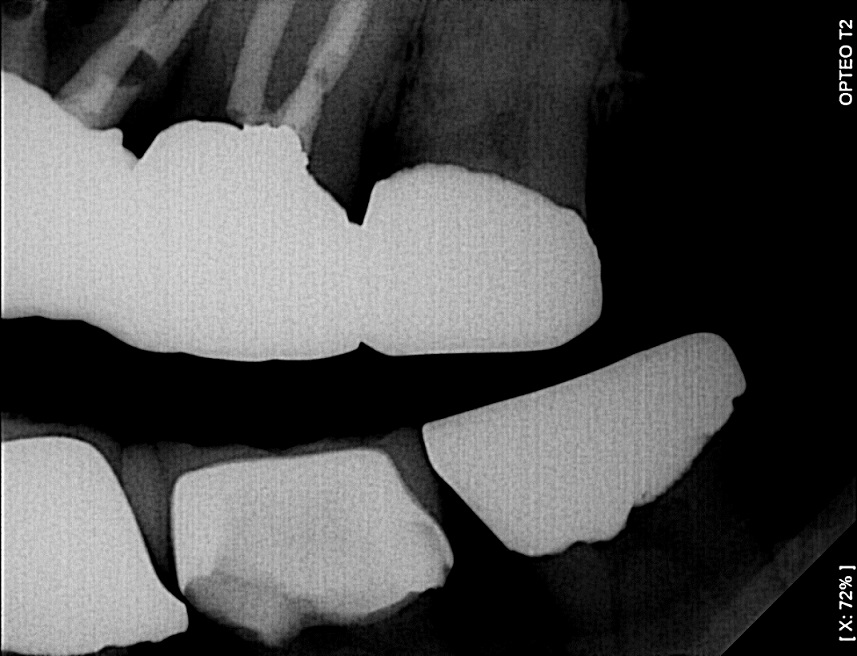

Dark High Contrast Images Problem

underexposed images show less than [X:80%] normally display light

Images are very dark, even below [80%], because the “auto contrast” is enabled in the sensor setup. This option corrects for imperfect exposure.

When the image is underexposed, even slightly, the “image processing” stretches the grey scale of the image to get better contrast (auto contrast or dynamic adjustment)